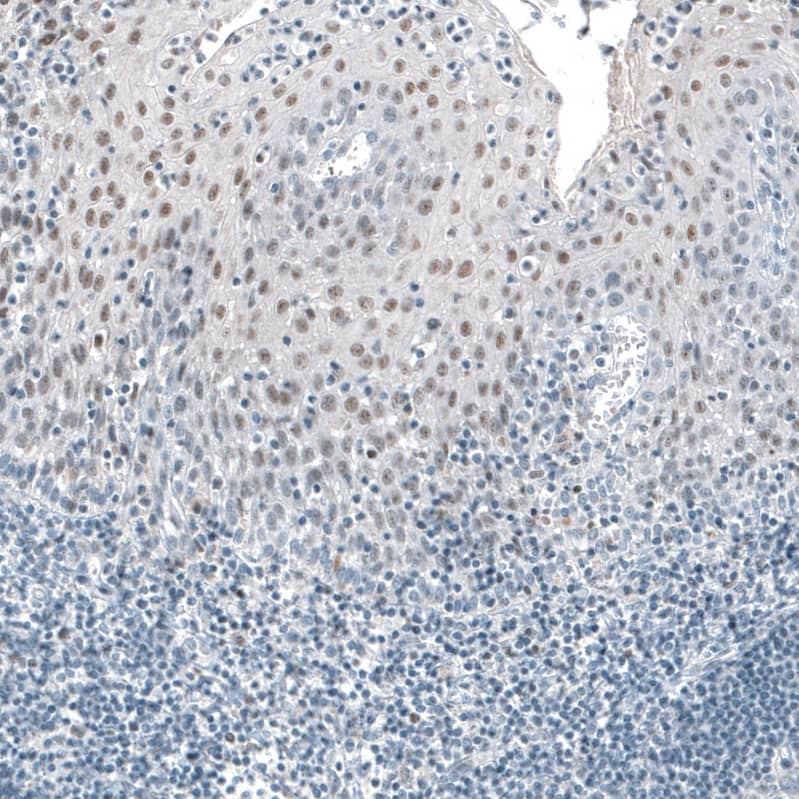

TET2 Antibody (CL6873) - BSA ...

TET2 Antibody (CL6873) - BSA Free

NBP2-76510

Applications:

WB, ICC/IF, IHC

Host:

Mouse Monoclonal